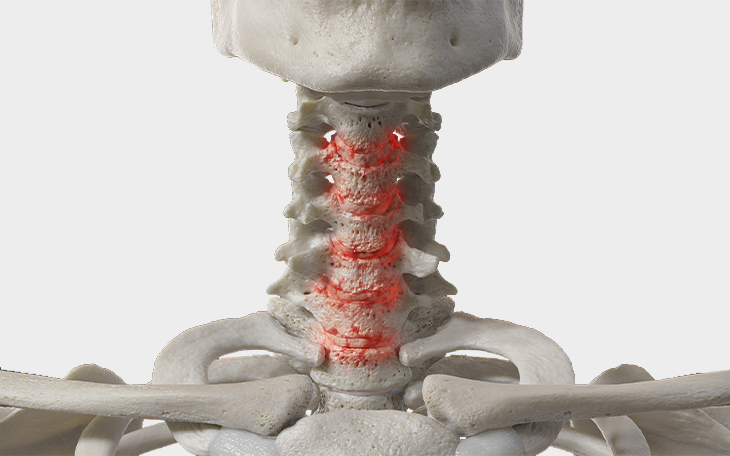

Erkrankungen der Halswirbelsäule

Die Halswirbelsäule (HWS) ist besonders beweglich und zugleich empfindlich gegenüber Fehlbelastungen und Verschleiß. In dieser Kategorie erhalten Sie einen Überblick über häufige Erkrankungen der HWS, deren Ursachen, Symptome und Therapiemöglichkeiten.

Eine Spinalkanalstenose bezeichnet eine Verengung des Wirbelkanals, in dem Rückenmark und Nerven verlaufen. In der Halswirbelsäule (HWS) ist der Raum für neurologische Strukturen enger als in der Lendenwirbelsäule, weshalb selbst mäßige Kompressionen zu Symptomen führen können. Wenn das Rückenmark betroffen ist, spricht man von einer Myelopathie, die sich durch Gangstörungen, erhöhte Reflexe, Spastik, Muskelschwäche und Sensibilitätsstörungen äußert. Der Verlauf ist meist schleichend, kann aber bei manchen Patienten auch rasch fortschreiten.

Ursachen